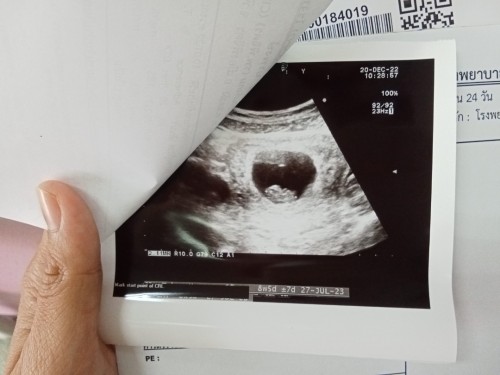

8วีค 5วันค่ะ

Post reply image

8วีค5วันค่ะ